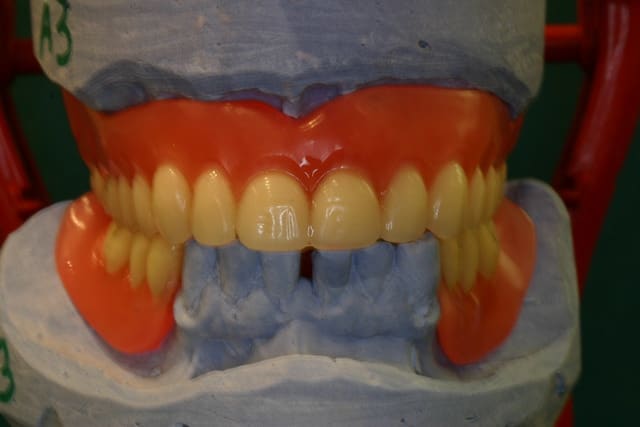

1.Bon... situation pré-extractionelle ( Je crois qu il faillait vraiment extraire )

2. Complet à essai en bouche après extraction et PRFs ds tous les alvéoles puis 3 séances d ostéotensions à venir pour le maxillaire

3. Vue sur articu

4. Télé de profil post-extractionelle

Bon la suite sera ostéotension mandibule et pose des implants mandibulaires en enfoui ds 45 j